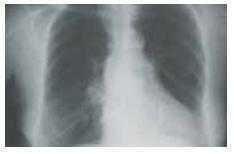

El estudio del paciente incluye, entre otras pruebas, gammagrafía ósea con 99mTc-MDP (figuras 1a, 1b y c), obteniendo imágenes de rastreo corporal completo y SPECT torácico, radiografía de tórax (figura 2) y ecocardiograma (figura 3).

Figura 2.